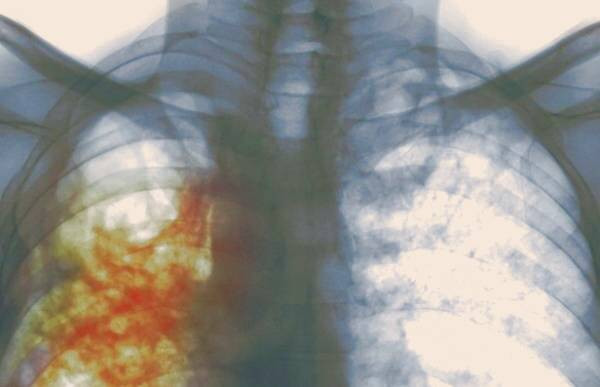

بیماری سل یک عفونت ریوی شایع و واگیردار است که به واسطه مایکوباکتریوم توبرکلوزیس، یا همان باسیل کخ، به وجود می آید. این پاتوژن قادر است از طریق ذرات معلق هوایی به افراد سالم منتقل شود و آنها را نیز به این بیماری مبتلا کند. بنابراین، سل ریوی به عنوان یک عفونت عمدتا عفونی و قابل انتقال میان افراد شناخته می شود که توسط باکتری مخصوص خود ایجاد و گسترش می یابد.

در بین تمامی موارد، آنهایی که مشکوک به سل ریوی هستند بیش از سایرین دیده می شوند. این بیماران اغلب سرفه های پایدار و متمادی را به مدت سه هفته یا بیشتر همراه با خلط خونی خواهند داشت. سل به دو نوع ریوی و خارج ریوی تقسیم می شود. علائم نوع خارج ریوی بسته به عضوی که مبتلا میشود متفاوت است و میتواند شامل موارد زیر باشد.

در سل ریوی انواع خلط ایجاد می شود. در آزمایش میکروسکوپی نیز میکروب این بیماری مشاهده خواهد شد. افراد مبتلا به آن ریوی می تواند این میکروب را از طریق هوا منتشر کند و باعث انتقال آن به سایرین شود از این رو باید قرنطینه باشد. همچنین علائم عمومی نیز در بیماران مبتلا به آن به وفور دیده می شود. نوع ریوی معمولا با یک سرفه آغاز می شود و گاهی اوقات یک درد مبهم در ناحیه قفسه سینه خبر از این بیماری می دهد. همچنین علائمی نظیر تب، لرز، درد عضلانی و تعریق نیز از دیگر علائمیست که در سل های ریوی و غیر ریوی دیده می شود.